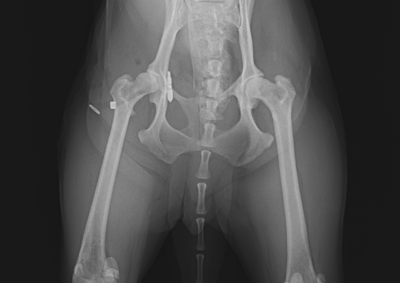

整形外科 注意 ボタンをクリックした先に、治療中および手術中の画像が説明で使用されている場合がございます。 そのような画像に弱い方は閲覧なさらないようお願いいたします。 整形外科 橈骨固定術 #251 整形外科 膝蓋骨高位に対する脛骨粗面遠位化術 整形外科 ミニチュアダックスの脛骨遠位内反矯正+膝蓋骨外方脱臼 整形外科 橈骨固定術 #250 整形外科 股関節脱臼に対するトグルロッド整復術 #64 整形外科 橈骨固定術 #249 整形外科 橈骨固定術 #248 整形外科 内側鉤状突起分離症 FCP 整形外科 橈骨固定術 #247 整形外科 膝蓋骨内方脱臼G3に対する人工滑車(PGR)#20 整形外科 CBLO #239 整形外科 股関節脱臼に対する大腿骨頭頸部切除術 <12345678910> 症例カテゴリー 放射線治療整形外科軟部組織外科脳神経外科内科腫瘍外科救急・集中治療リハビリテーション科腫瘍内科内視鏡科脳神経科呼吸器外科中医・漢方猫の腎移植循環器科